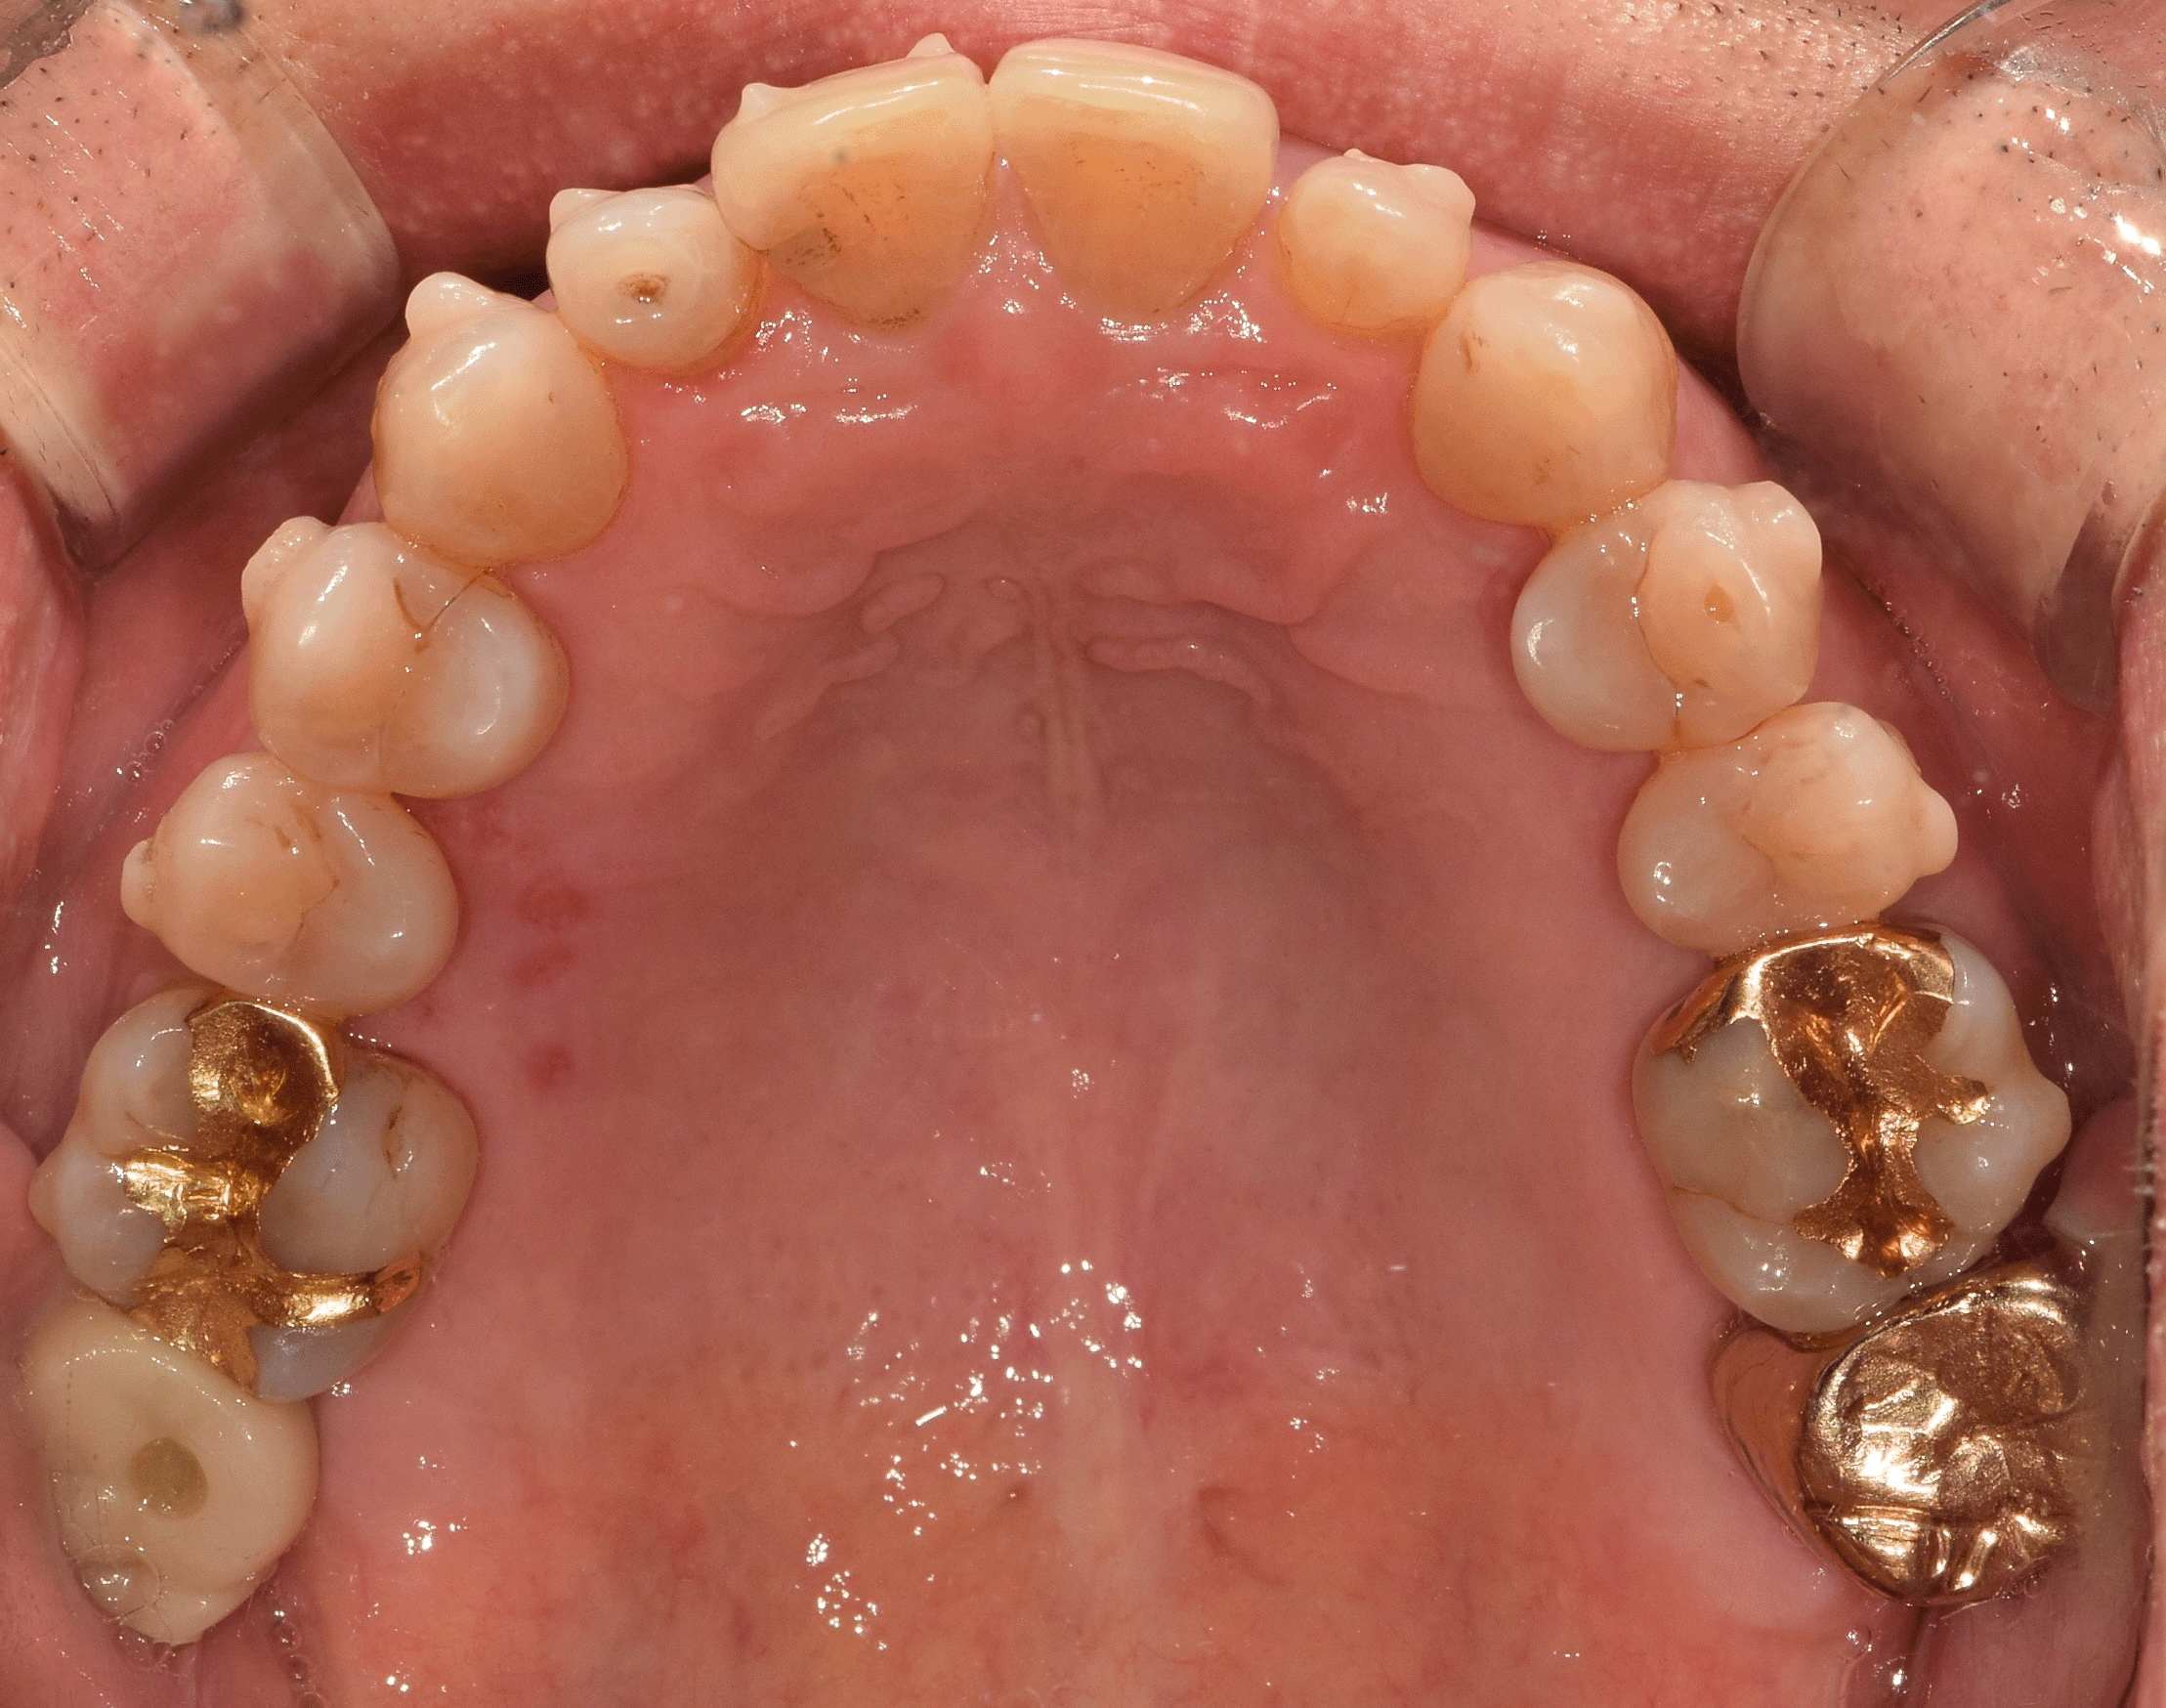

4. 마무리

치료가 어느 정도 끝나가면

쉐이드 가이드를 통해

환자의 주변치와 비슷한 색상을 골라

크라운을 제작합니다.

크라운은 다른 재료에 비해

탈락률이나 부작용이 적으니 걱정하지 마세요.

앞니이기에 크기, 마모도, 투명도를 전부 고려하여

균형감 있는 치아로

왜소치가 개선된 모습을 확인할 수 있습니다.

전체적으로 보았을 때 깔끔하게 정리된 모습이며,

주변 이들과도 자연스럽네요.

교정까지 함께 진행된 증례이기에

더욱더 심미적으로 보입니다 ^^